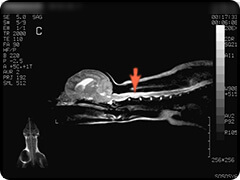

- 脊髄空洞症

- 脊髄内に空洞が生じた状態で、空洞内には脳脊髄液と同様の液体が満たされています。

疼痛がでたりふらつきや不全麻痺など症状は様々です。 -

頸部の脊髄です。水っぽいところが白く映っています。

水っぽいところは黒く映っています。